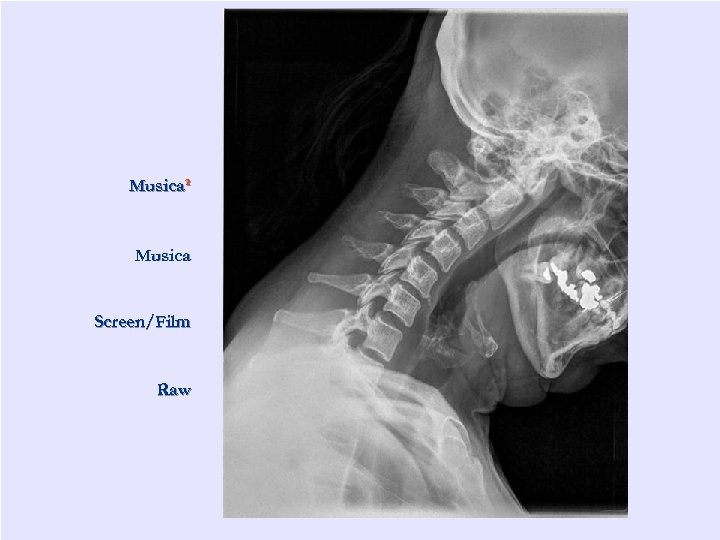

Возможность обработки

Musica² Musica Screen/Film Raw "Сибирский успех" www. uspekh. ru